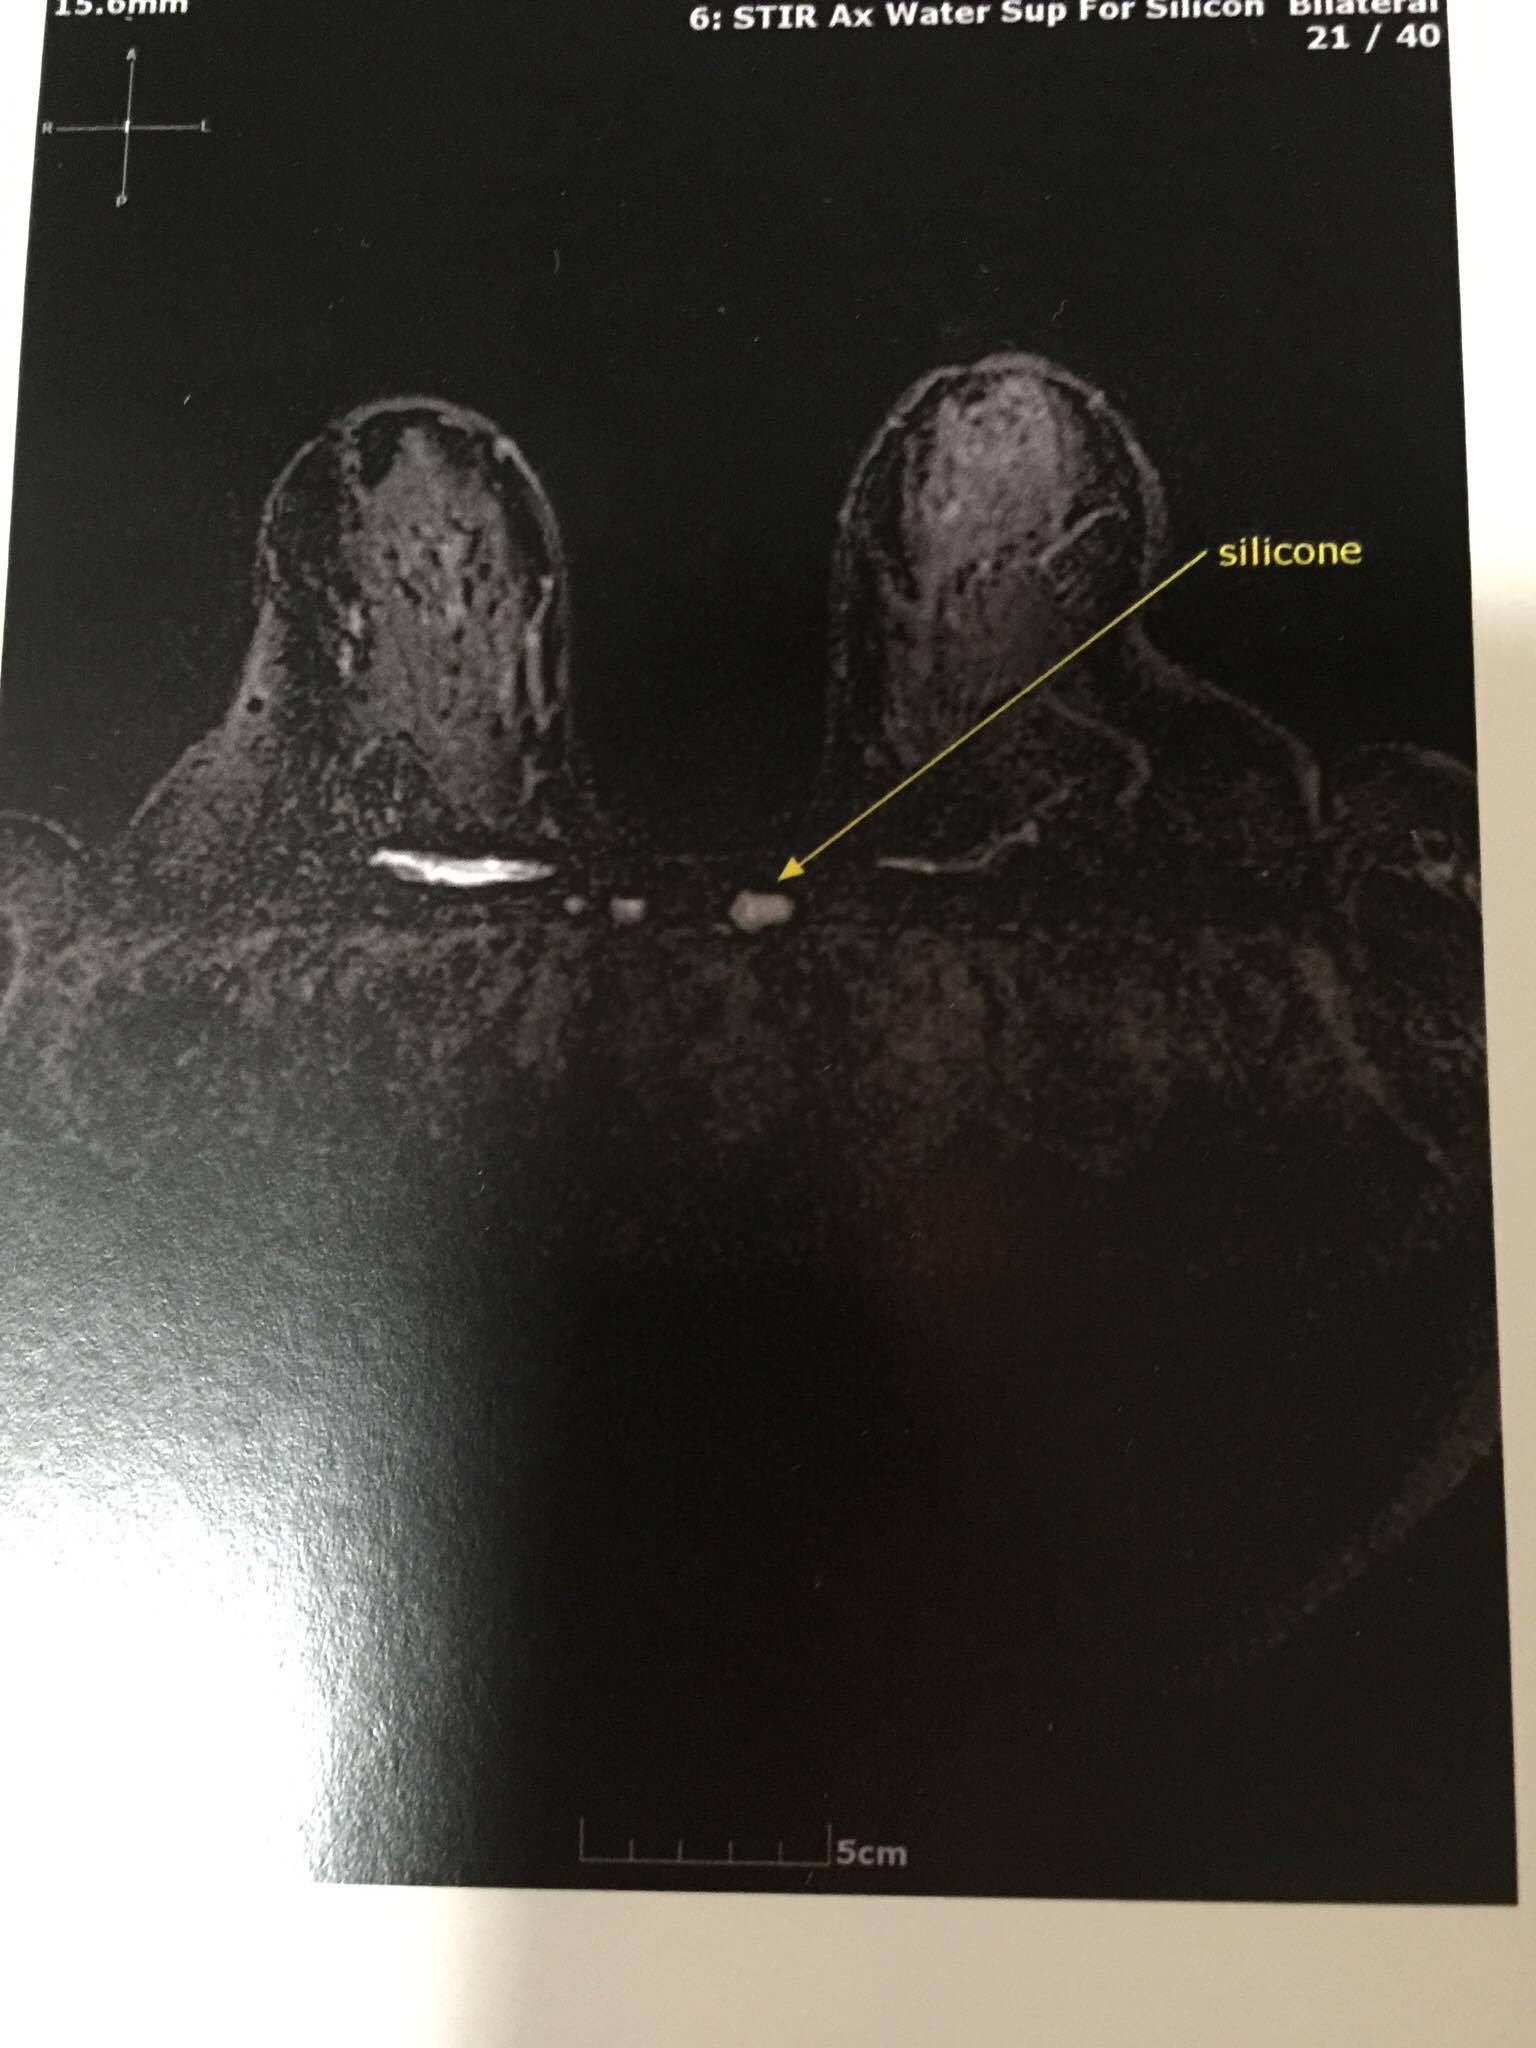

Photo above: This woman has silicone migrated throughout her lymph system and chest wall .. an MRI scan revealed there is a pocket of silicone over hear heart. #toxicPIPs

Above photo: This is just one view of many which show extensive migrated silicone